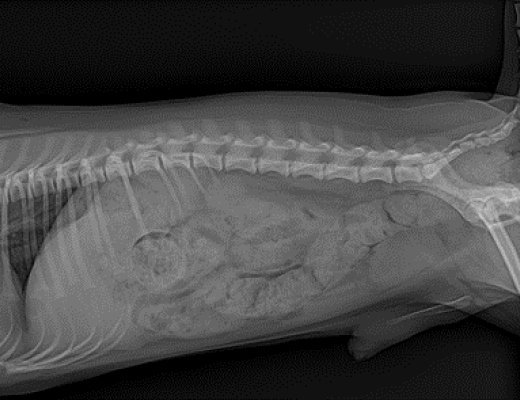

· 방사선 검사

방사선 검사는 방사선 상에서 확인될 수 있는 결석의 개괄적인 위치 파악에 있어 중요하게 작용합니다. 방사선 상 명확하게 보이는 결석 또는 이차적인 신장의 비대 소견이 확인되게 되면, 실제 신장 및 요관에서 발생한 형태 변화를 확인하기 위해 초음파 검사를 진행하게 됩니다.